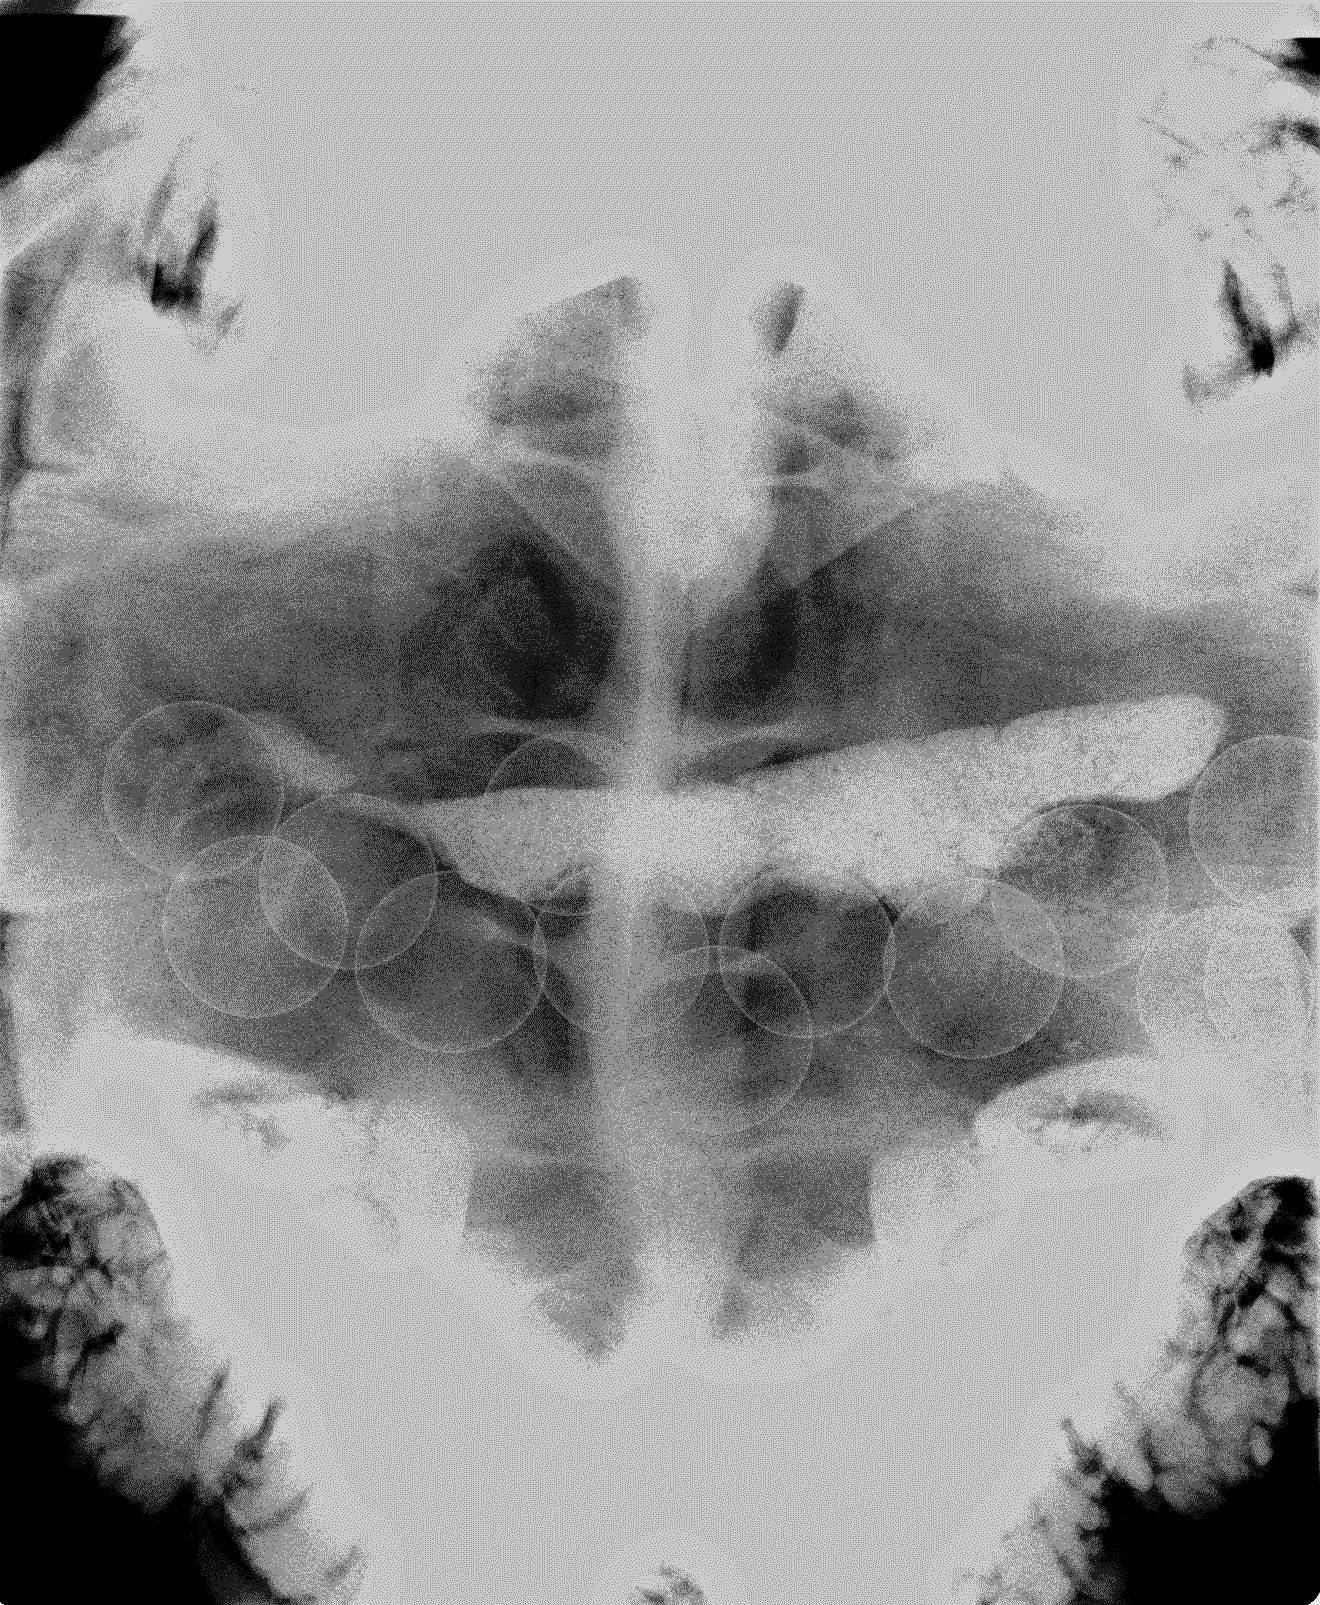

その時のレントゲン写真がこれ。

よく見ると...お腹の中に小さな丸い物がたくさん!その数、数えられただけで21個!

何をお腹に抱えているのか...そう、卵がたくさんお腹の中にあったのです。

ちなみに真ん中あたりに横に細長く白く見えるものは糞の塊です。